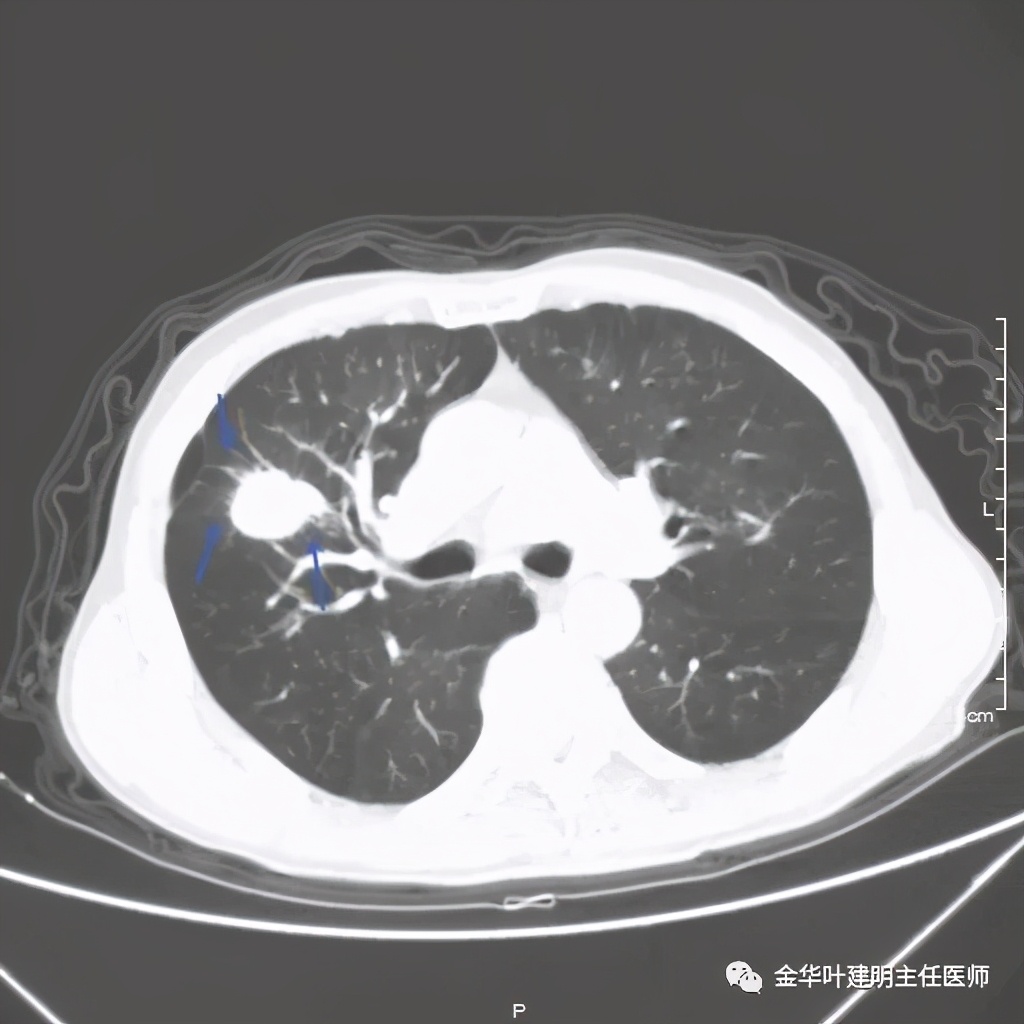

上图是穿刺时的某个层面,病灶的细毛刺征比较明显(蓝色箭头),病灶的边缘是不平的,而且有细短的毛刺样突向周围肺组织,这可是恶性的特征

桔色箭头示病灶周围血管征明显,有较粗的血管进入病灶,较细的也有